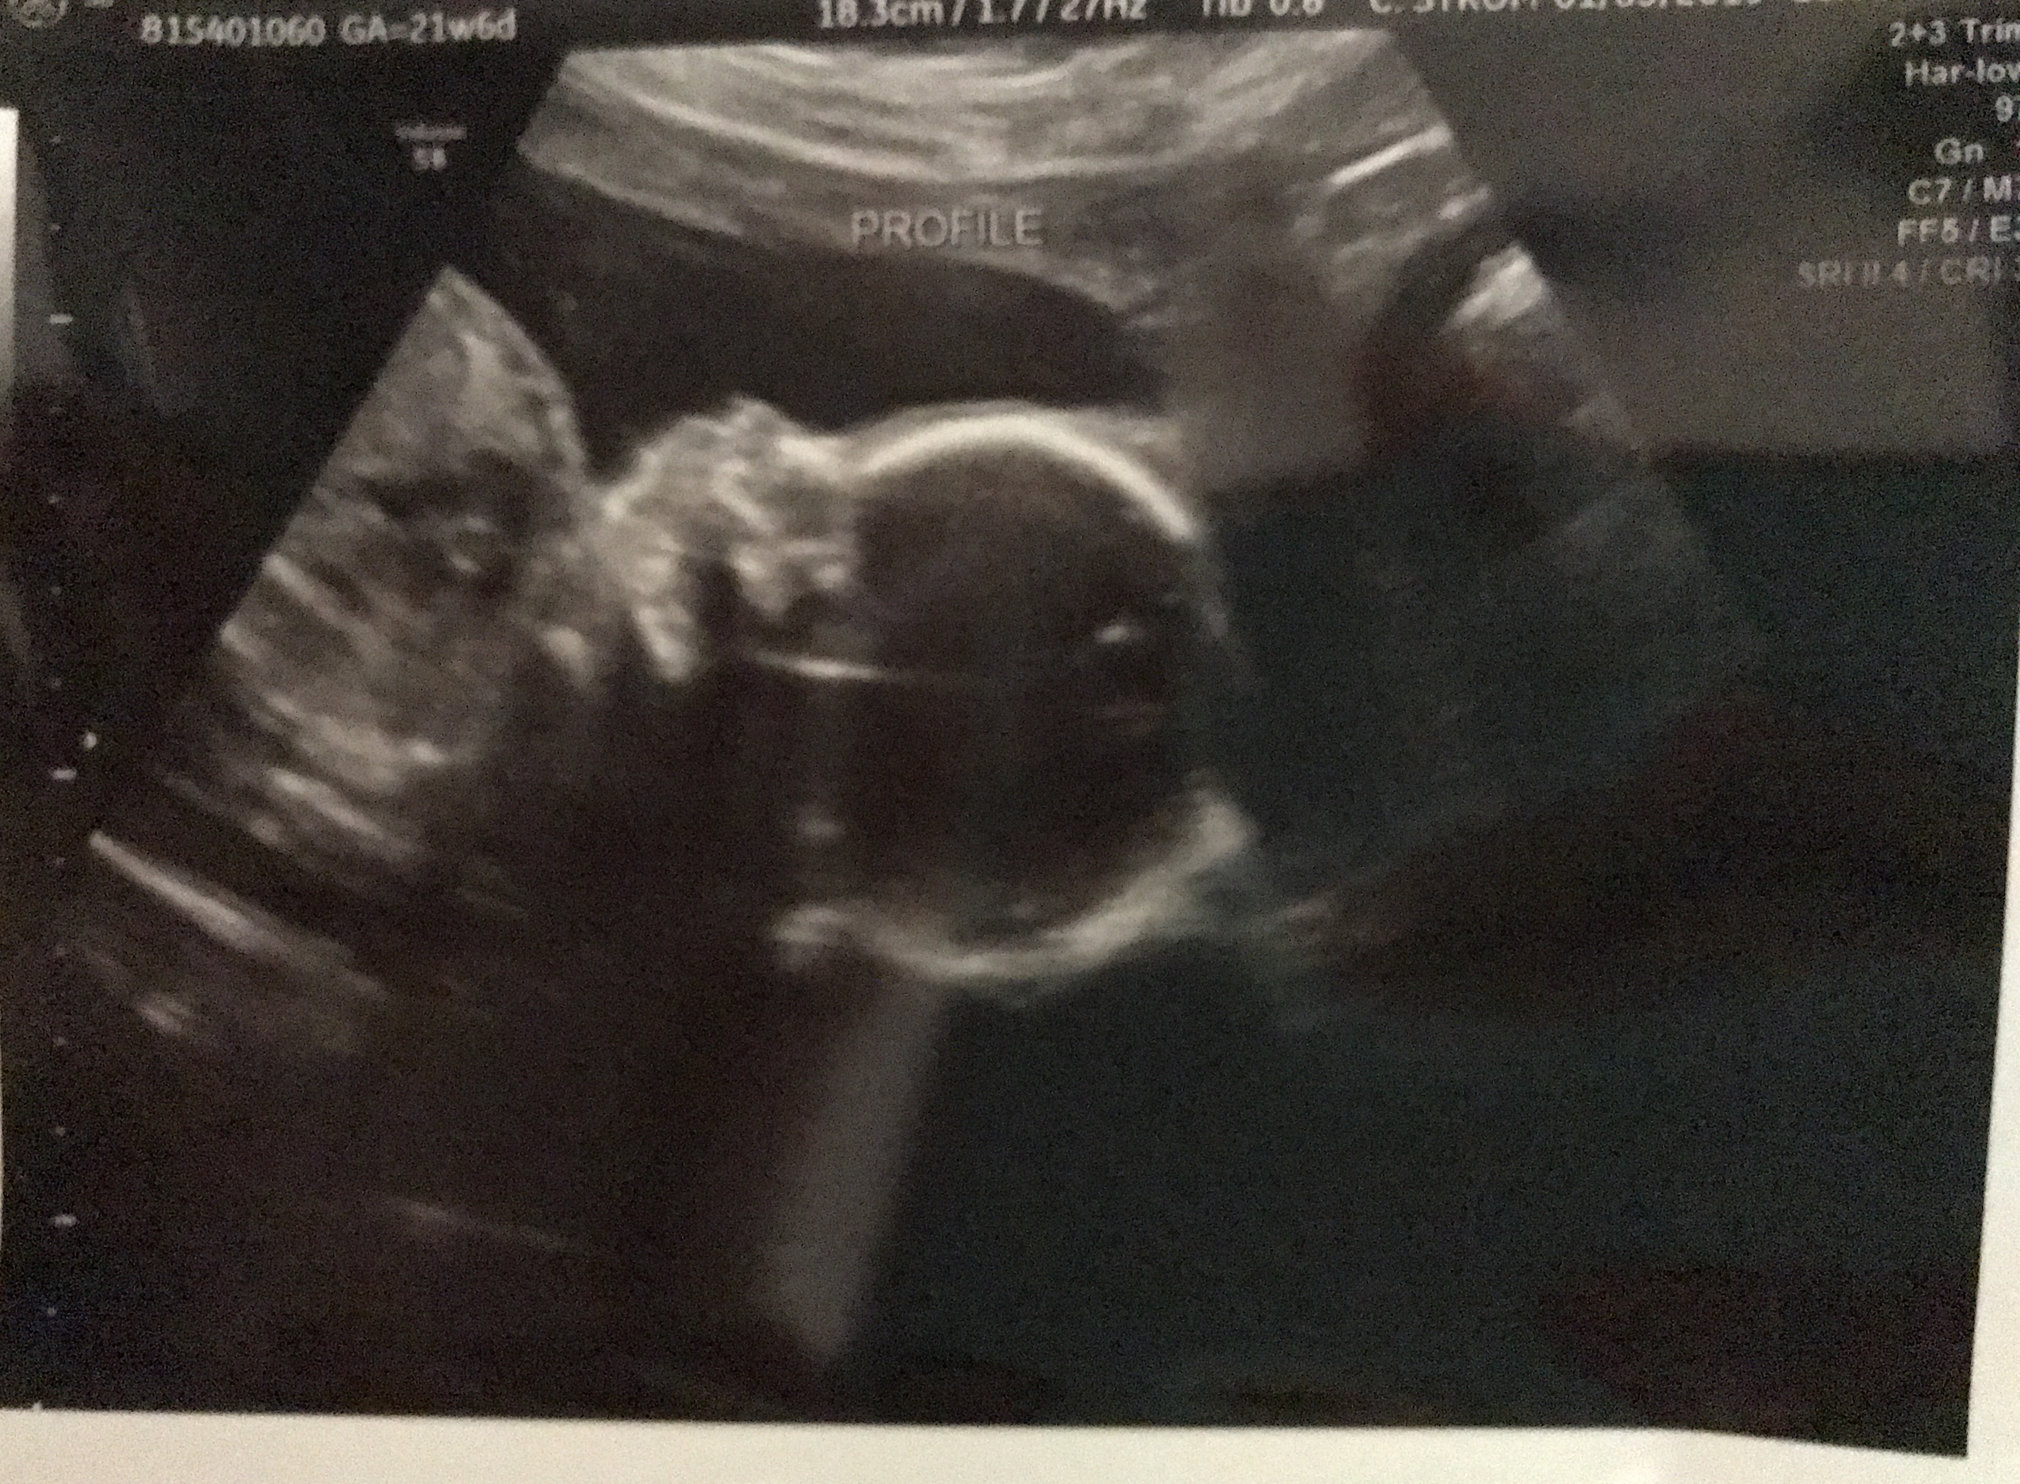

Anatomy scan today at 21W5D (they say 21W6D, but I know when I ovulated). Other than a calcium deposit found in the heart, everything looked good. Kind of stressed about it but hoping for the best.